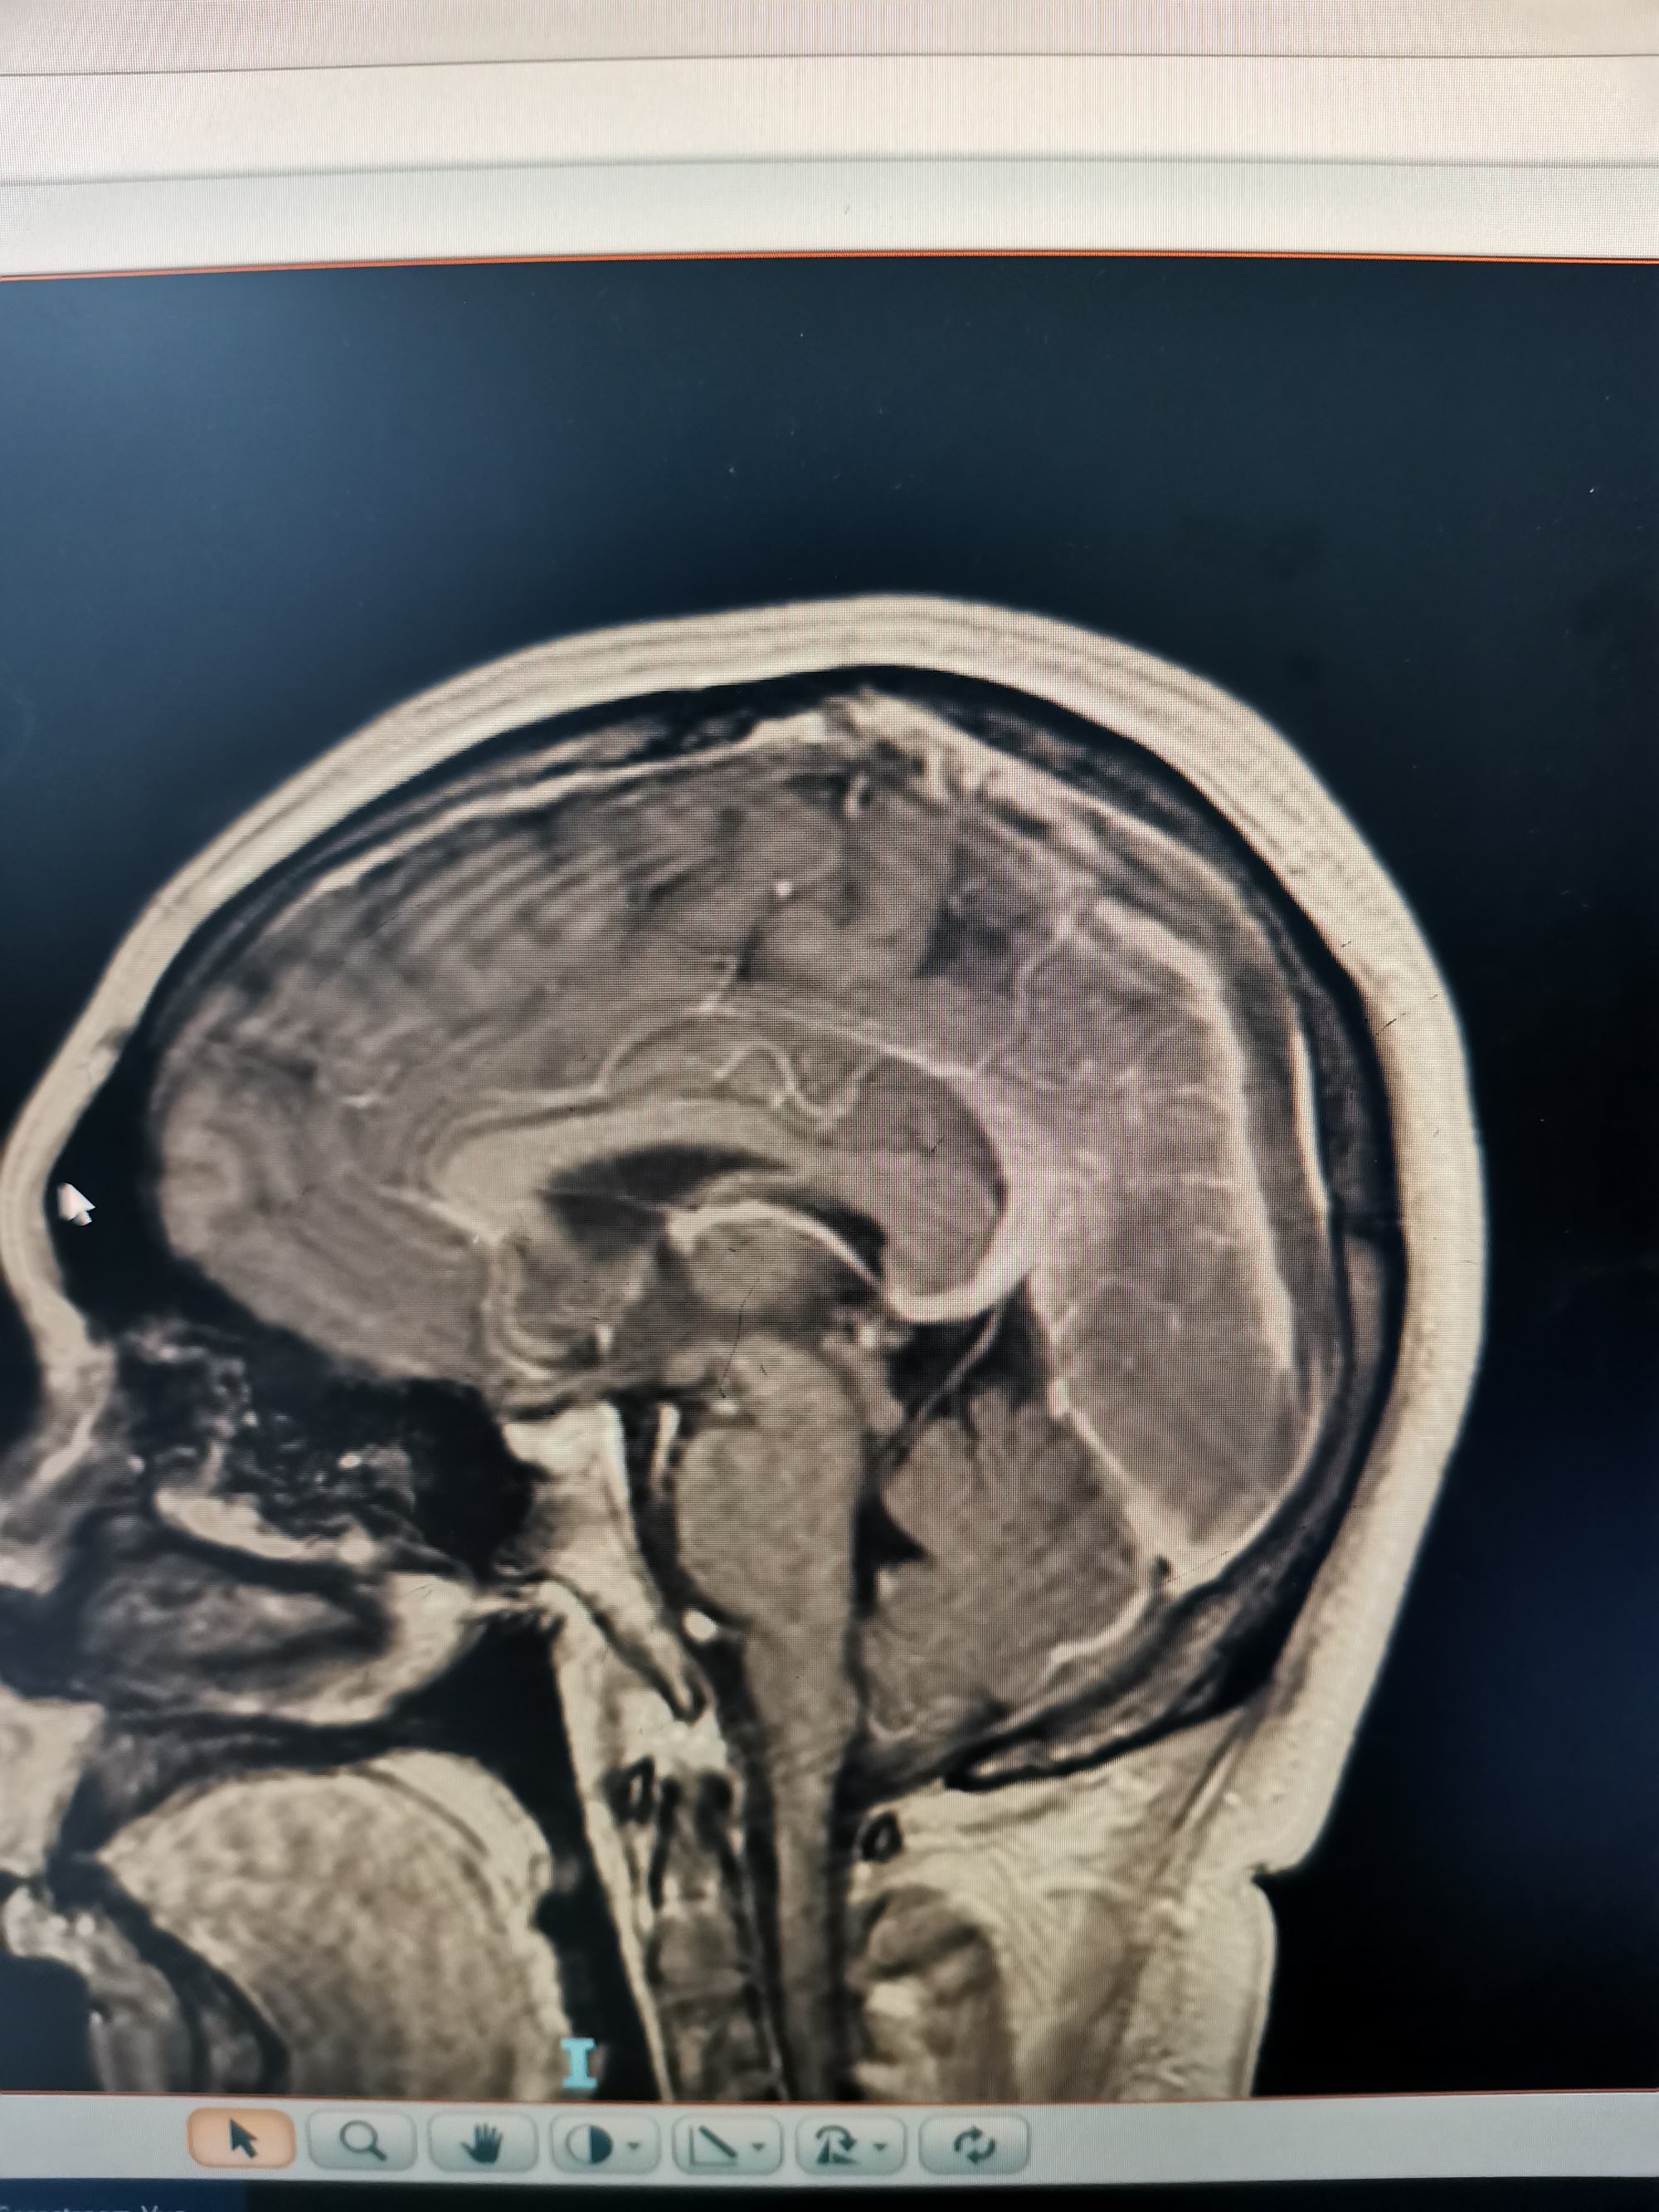

外院磁共振增强见,矢状窦局部充盈缺损。

增强显示矢状窦长节段充盈缺损,D-2聚体大于正常上限5倍以上。我科诊断考虑上矢状窦血栓形成伴多发多次脑梗死伴出血。

矢状窦全程血栓,与外院相比血栓明显扩大。立即急诊行脑血管造影+介入取栓术。

矢状窦是大脑最大的回流静脉,相当于颅内的长江,长江主干闭塞,各支流必将洪水泛滥。患者随时可能再发脑梗和脑出血可能。立即急诊行脑血管造影+介入取栓术。

患者左侧横窦优势,左侧颈内动脉造影侧位见矢状窦起始部至横窦水平未显影。